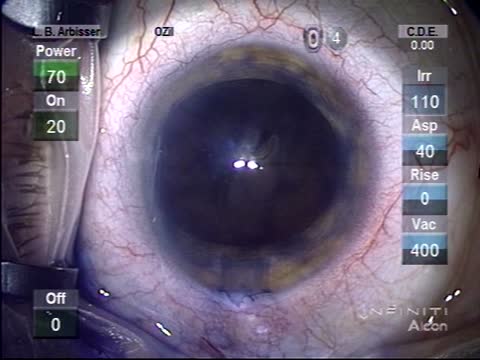

Intumescent Cataract

Lisa Brothers Arbisser, MD